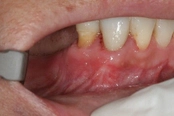

Lower molar failed root canal, microsurgery saved the tooth:

Before

Immediately after

3-month follow-up with complete healingThis patient presented with a failed root canal. The root canal became infected. An apicoectomy (apical microsurgery) was performed using the laser. Patient had minimal swelling, minimal discomfort, and fast healing. The tooth was saved and an implant avoided. This tooth tends to have a lower success rate with root canal therapy; thankfully apical microsurgery was available to save the tooth.

At the 3 month follow-up, the gums look like nothing was done thanks to the skill and use of the laser for the procedure.